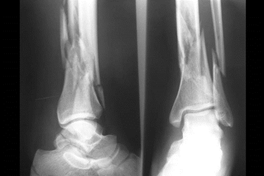

We reviewed the radiological results of patients treated in our institution for closed fractures of the distal tibia during the period January 2013 to December 2017. Ethical clearance was obtained from the university’s research and ethics committee (Ref 422/2022), we included fractures classified as AO 43A10 and fractures that are 4-11cm above the tibial plafond (Figure 1 & 2). We excluded segmental fractures, intraarticular fractures, fractures in patients less than 18yrs of age, pathological fractures, patients with previous fractures of the tibia and fractures treated by any method other than the two under investigation.

Figure 1 AO Classification.

Figure 2 Distal tibia fracture.